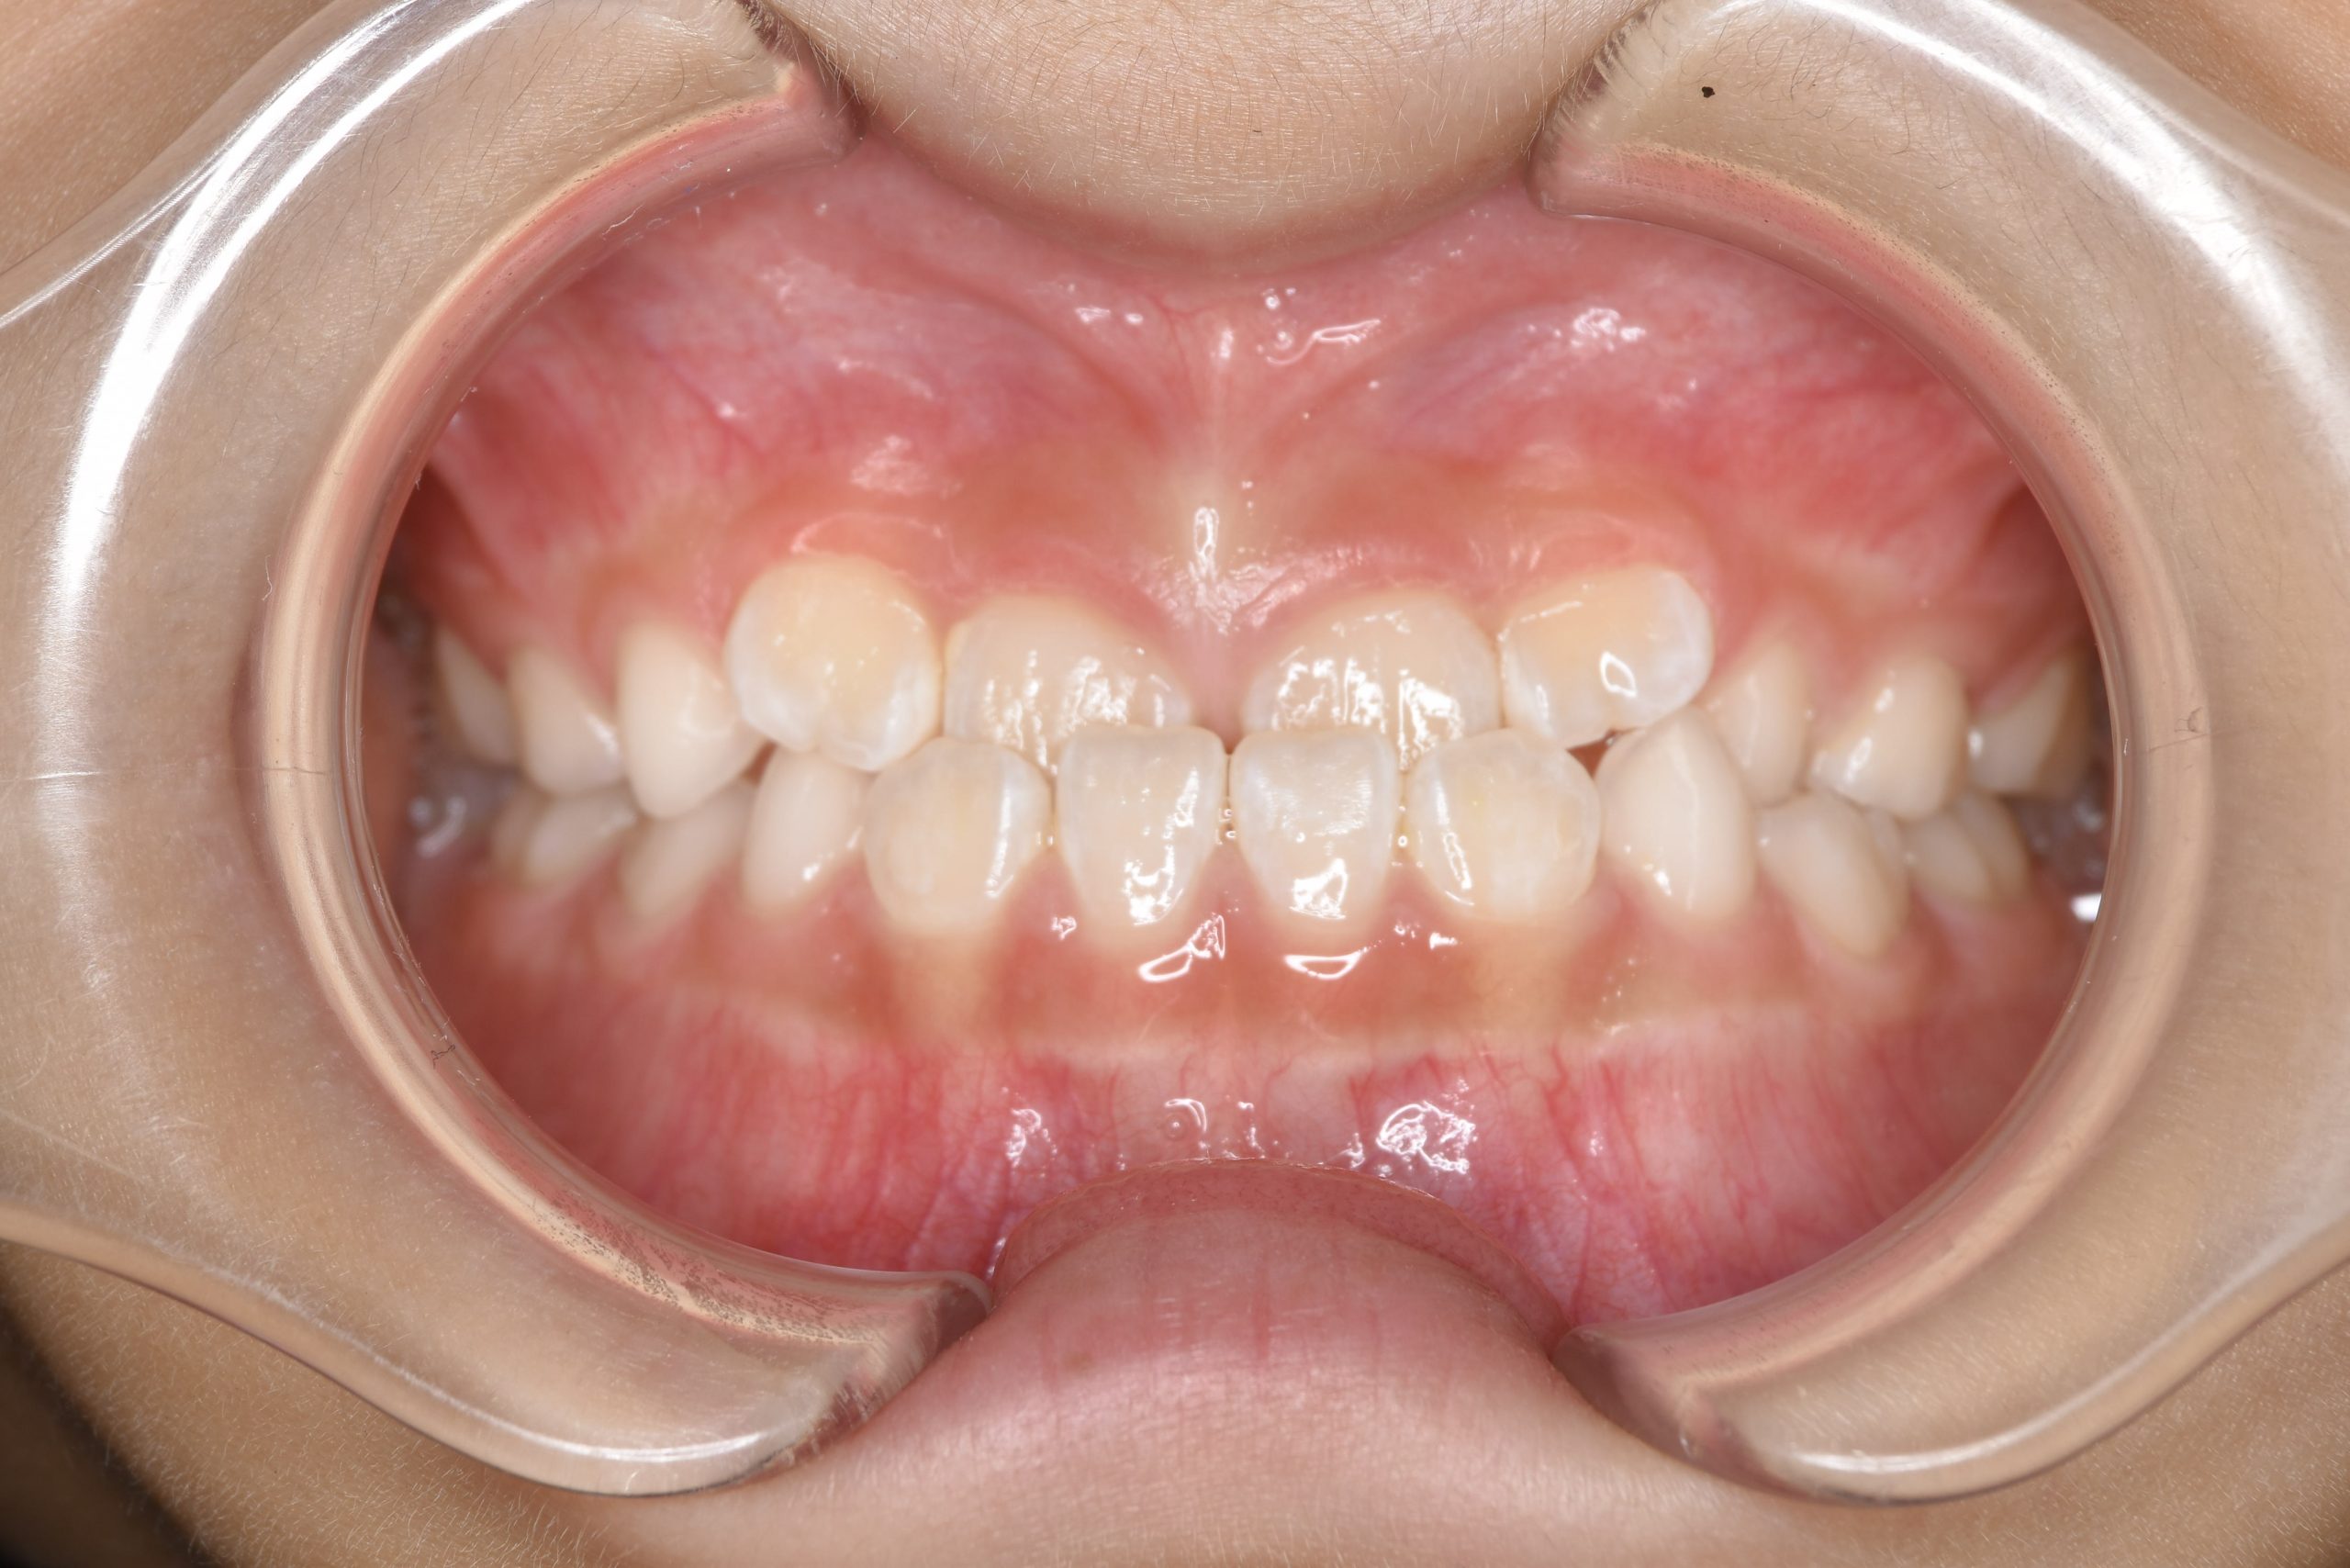

子どもの矯正治療|症例_858 Case

ビフォー

主訴 下顎が出ている

施術内容 上顎急速拡大装置と下顎リンガルアーチを用いて上下顎骨を拡大した。

上顎前方牽引装置を用いて上顎骨を前方に成長促進させた。

その後マウスピース型矯正装置で歯牙を配列し良好な咬合を獲得した。

治癒期間 1年6か月 ※経過観察含む